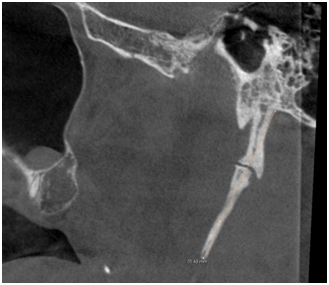

The morphology of SHC was recorded to evaluate the general structural appearance and the number of segments and was categorized into 3 types as single segment ossification, two segment ossification and three segment ossification (Figures 1‒3). The length was defined as the distance between the base of the SP and the tip of the ossified SHC. If there was segmental ossification of the SP, the distance was measured including the non-ossified parts (Figure 4). The antero posterior angle (APA) was defined as the angle made by the process with the perpendicular dropped from the lateral part of the external auditory meatus (Figure 5). The mediolateral angulation (MLA) was defined angle of intersection between the longitudinal axis of the SHC to the perpendicular dropped from the base of the process (Figure 6).

Figure 4 shows measurement of length from base to tip of SP.